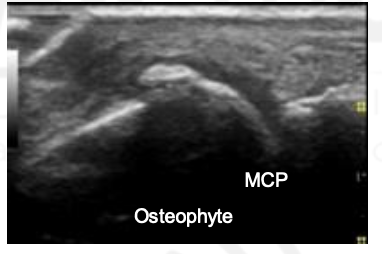

What is this?

Osteophyte

Do not be suprised to see synovial hypertrophy and effusion in OA hand joints on US exam.